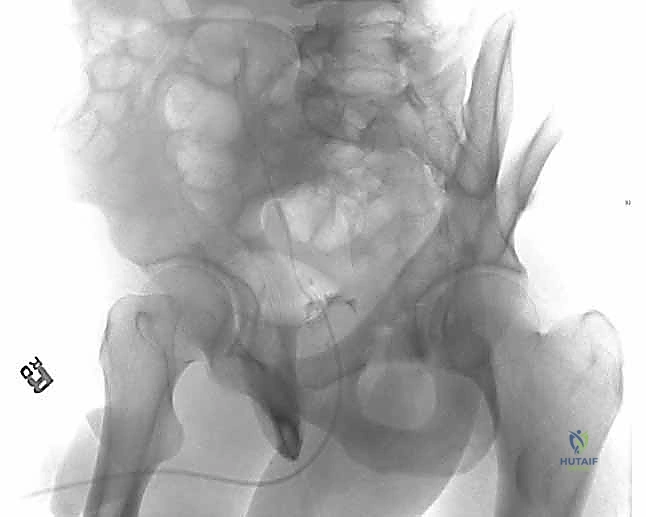

1. التحضير والتخدير

تُجرى العملية تحت التخدير العام أو النصفي. يتم وضع المريض على طاولة العمليات في وضعية الاستلقاء الجانبي أو على البطن، حسب النهج الجراحي المختار. يتم استخدام جهاز الأشعة السينية القوسي (C-arm) داخل غرفة العمليات لتوجيه الجراح خطوة بخطوة.

2. النهج الجراحي (Surgical Approach)

النهج الأكثر استخداماً لكسور الجدار الخلفي هو نهج كوخر-لانغنبك (Kocher-Langenbeck Approach). يقوم الدكتور هطيف بعمل شق جراحي دقيق في منطقة الأرداف للوصول إلى الجزء الخلفي من مفصل الورك. يتم فصل العضلات بلطف شديد، مع التركيز الأقصى على تحديد العصب الوركي وعزله وحمايته طوال فترة العملية لتجنب أي تلف.

3. تنظيف المفصل (Joint Debridement)

بمجرد الوصول إلى المفصل، إذا كان هناك خلع، يتم رد رأس الفخذ بلطف. الخطوة الحاسمة هنا هي فحص داخل المفصل بدقة متناهية لإزالة أي شظايا عظمية أو غضروفية صغيرة قد تكون محشورة بالداخل. بقاء أي شظية سيؤدي إلى تدمير الغضروف بشكل سريع ومؤلم.